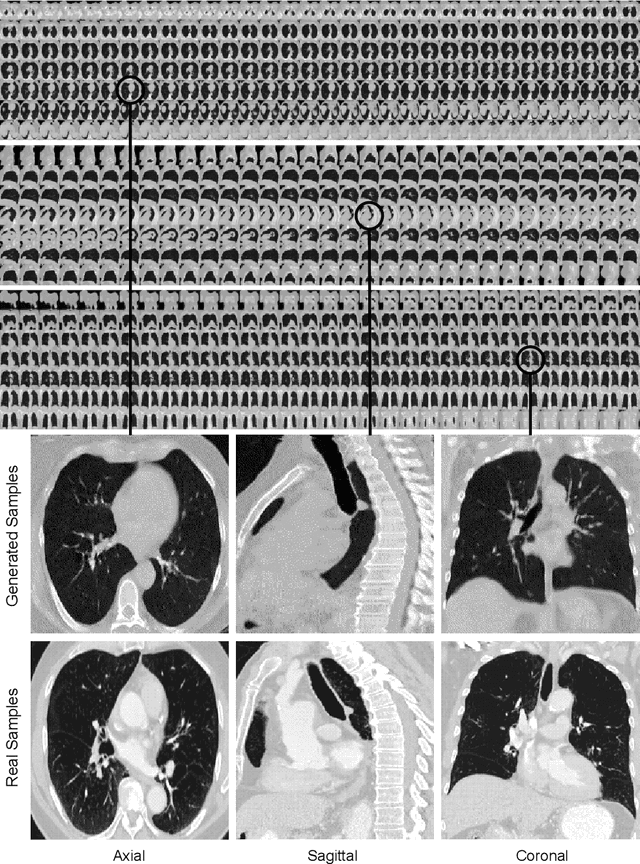

Abstract:Diversity in data is critical for the successful training of deep learning models. Leveraged by a recurrent generative adversarial network, we propose the CT-SGAN model that generates large-scale 3D synthetic CT-scan volumes ($\geq 224\times224\times224$) when trained on a small dataset of chest CT-scans. CT-SGAN offers an attractive solution to two major challenges facing machine learning in medical imaging: a small number of given i.i.d. training data, and the restrictions around the sharing of patient data preventing to rapidly obtain larger and more diverse datasets. We evaluate the fidelity of the generated images qualitatively and quantitatively using various metrics including Fr\'echet Inception Distance and Inception Score. We further show that CT-SGAN can significantly improve lung nodule detection accuracy by pre-training a classifier on a vast amount of synthetic data.